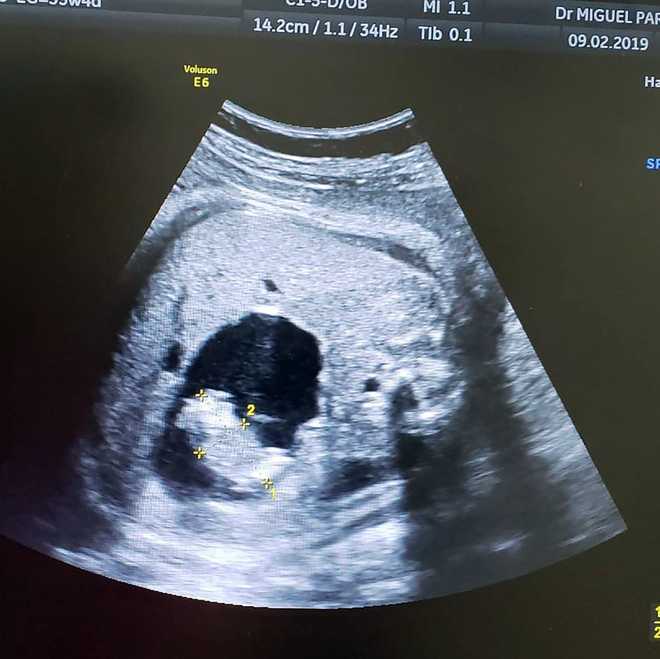

The twin fetus.

Originally, doctors thought that the fetus had a cyst on her liver. But that changed when the mother, Monica Vega, visited Dr. Miguel Parra-Saavedra, a high-risk pregnancy specialist in Baranquilla, Columbia. Parra-Saavedra was able to see that was believed to be a cyst was actually a tiny infant who was "supported by a separate umbilical cord drawing blood where it connected to the larger twin’s intestine," per . The connection through the umbilical chord is why the smaller fetus is frequently known as a parasitic twin, according to The Times.

This was discovered at 35 weeks' gestation, five weeks before full-term birth, which sets this fetus-in-fetu case apart from others that have occurred over the past few years, such as those in and .

Two weeks later at 37 weeks gestation, Vega gave birth via cesarean section to a 7-pound baby girl named Itzamara. One day later, the newborn underwent laparoscopic surgery to remove the fetal twin, who measured at about 2 inches long, Parra-Saavedra told .